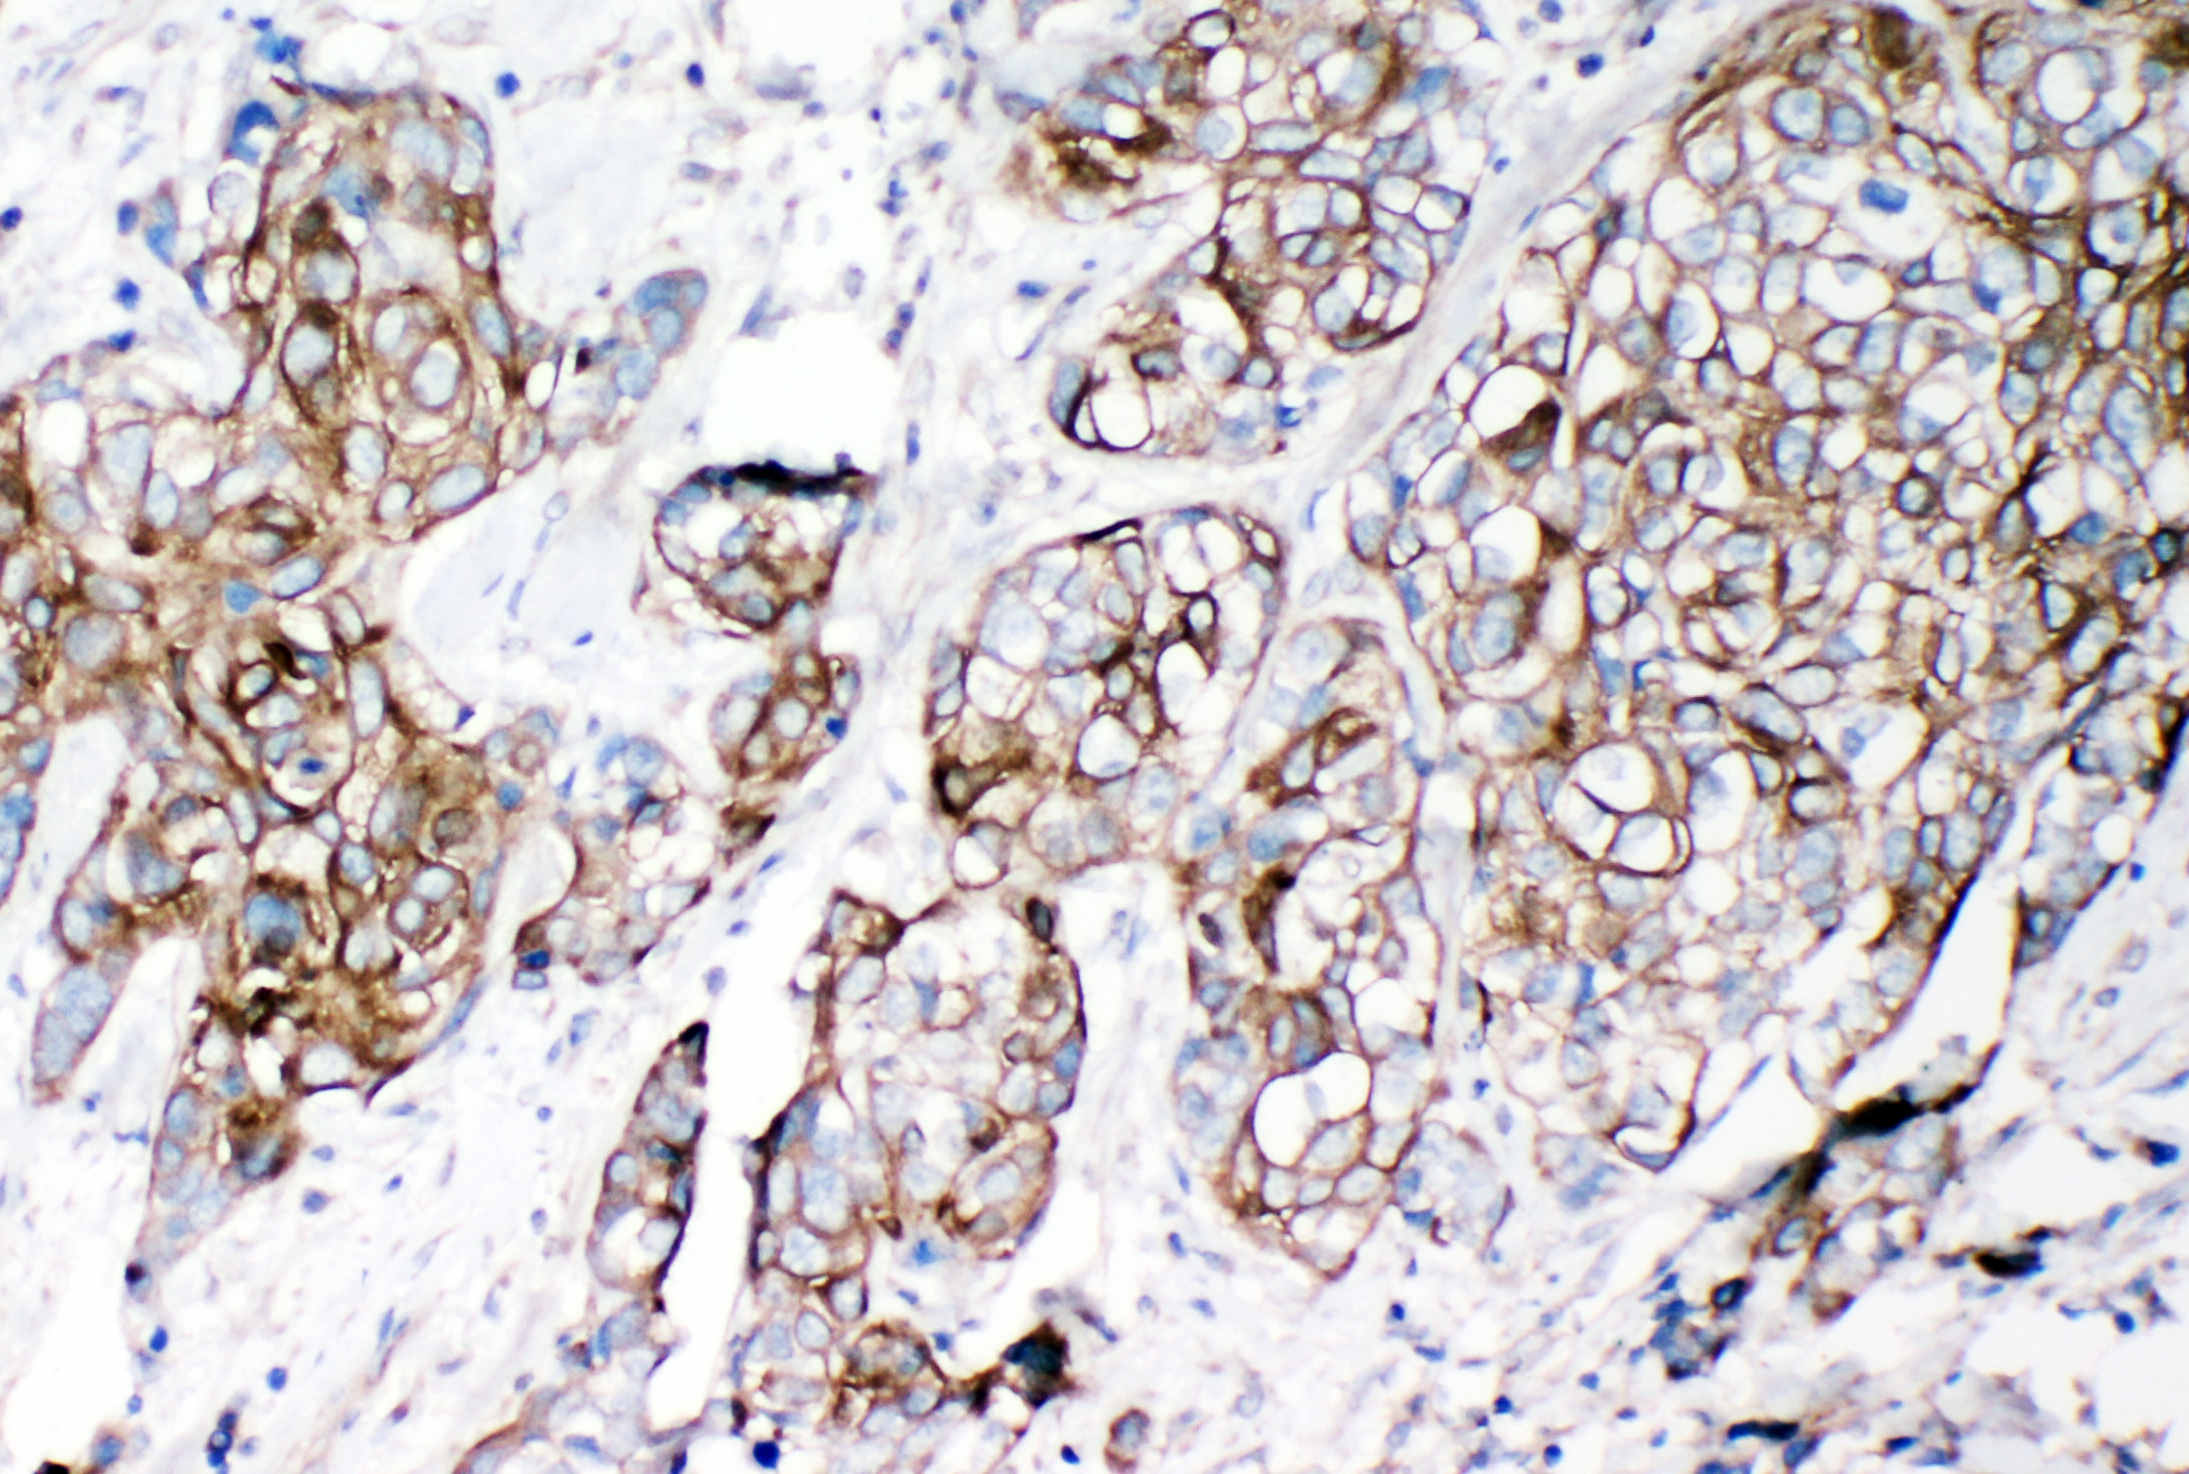

IHC analysis of VE-Cadherin/CDH5 using anti-VE-Cadherin/CDH5 antibody (BA3032).

VE-Cadherin/CDH5 was detected in a paraffin-embedded section of human lung cancer tissue. Biotinylated goat anti-rabbit IgG was used as secondary antibody. The tissue section was incubated with rabbit anti-VE-Cadherin/CDH5 Antibody (BA3032) at a dilution of 1:200 and developed using Strepavidin-Biotin-Complex (SABC) (Catalog # SA1022) with DAB (Catalog # AR1027) as the chromogen.